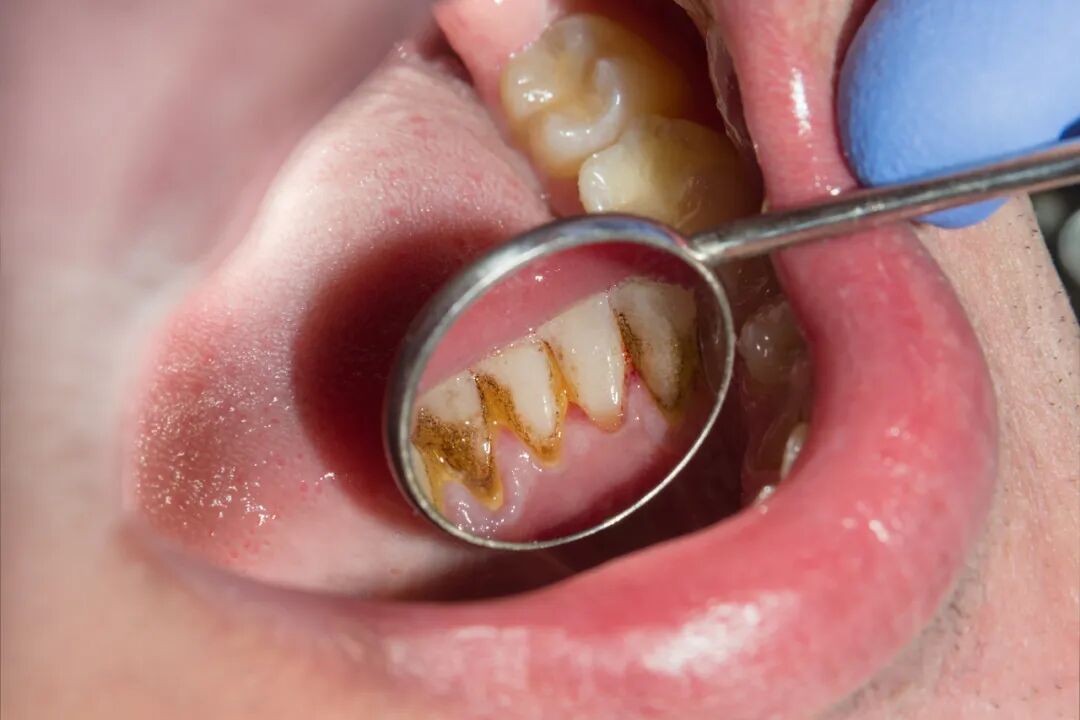

试着照照镜子,尤其关注那些平常刷牙时照顾不到的死角、牙缝、牙龈边缘。

是否能看见紧紧吸附在牙齿上的一些黄黄的,或者是褐色、黑色的小硬物?

图片来源:视觉中国

这就是牙结石,它本身并不可怕,可怕的是它的存在率太高了,相关数据显示[1]

15 岁人群,牙结石检出率高达 73.6%;

35~44 岁人群,牙结石检出率高达 96.7%;

55~64 岁人群,牙结石检出率高达 96.4%。